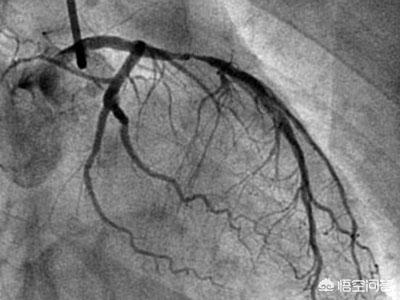

1) La coronarographie est en effet l'examen de référence pour le diagnostic de la maladie coronarienne. Il s'agit d'un examen dynamique qui permet d'identifier clairement l'emplacement des lésions sténosantes dans les différentes branches des artères coronaires et d'estimer leur étendue ainsi que l'irrigation sanguine de l'ensemble du vaisseau. Cependant, il s'agit d'un examen invasif, qui doit être réalisé par l'artère fémorale ou l'artère radiale, et le coût relatif de l'examen est plus élevé, de sorte que certains patients ne sont pas aptes à subir cet examen.

Tout d'abord, il faut préciser que la coronarographie n'est qu'un test, un test important pour évaluer la gravité de la maladie coronarienne, le traitement de la maladie coronarienne, l'effet du traitement de la maladie coronarienne et pour déterminer si la maladie coronarienne est présente. Ainsi, pour de nombreux patients chez qui on a diagnostiqué une maladie coronarienne, afin de clarifier l'effet du traitement de la maladie coronarienne et d'évaluer la gravité de la maladie coronarienne, nous devons souvent choisir d'examiner l'angiographie coronarienne afin d'évaluer l'état de la maladie et de guider le traitement.

La coronarographie est l'une des méthodes de référence pour confirmer le diagnostic de maladie coronarienne et joue un rôle très important dans la détermination du degré de sténose des artères coronaires. Pour les patients atteints d'une maladie coronarienne due à l'athérosclérose des artères coronaires, dans les conditions médicales actuelles, il n'y a pas de remède efficace, un traitement à long terme est nécessaire, afin de stabiliser et de contrôler l'état et de réduire l'apparition de complications, nous devons prêter attention à la surveillance des changements de l'état et à l'examen régulier en même temps que le traitement régulier, et adhérer à l'examen régulier du contrôle de l'état et à l'élaboration d'un programme individualisé a un rôle irremplaçable, afin que les patients atteints d'une maladie coronarienne puissent bénéficier d'un traitement de qualité. Les patients atteints d'une maladie coronarienne doivent faire l'objet d'un examen régulier.